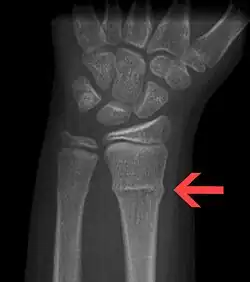

A radiograph image of a torus (buckle) fracture

A Torus fracture, also known as a buckle fracture is the most common fracture in children.[1] It is a common occurrence following a fall, as the wrist absorbs most of the impact and compresses the bony cortex on one side and remains intact on the other, creating a bulging effect.[2] As the bulge is only on one side of the bone, this injury can be classified as an incomplete fracture. The compressive force is provided by the trabeculae and is longitudinal to the axis of the long bone, meaning that the fracture itself is orthogonal to that axis.[3] The word "torus" originates from the Latin word "protuberance."[4]

Buckle fractures can be identified by performing a radiograph. The diagnosis of a torus fracture is made from both anterior/posterior and lateral projections. The typical features include:

• The buckling of cortical bone, which may appear as a small bulge or protuberance in the radius or ulna.

• The bone may have a slight angulation.[8]